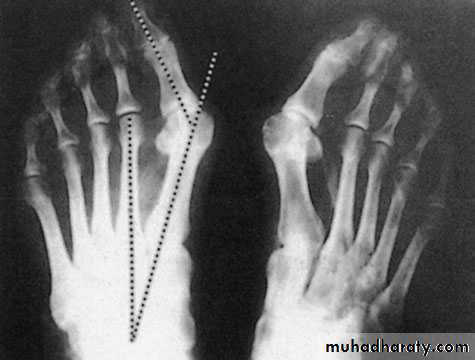

Metatarsus primus varus: there is forefoot splaying with excessive primary varus position of the 1st. metatarsal bone that predispose for lateral deviation of the big toe during shoe wear.

Inter metatarsal angle less than 9 digree &metatarsophal angel angle less than 15 digree

X-ray:

Taken with the patient standing to show the degree of metatarsal and hallux angulations.Also it shows the state of the joint being normal, arthritic or subluxated.

1. Adolescent congenital deformity always need surgical correction of the varus position of the 1st. metatarsal by osteotomy to put it more straight so the big toe will assume more straight position.